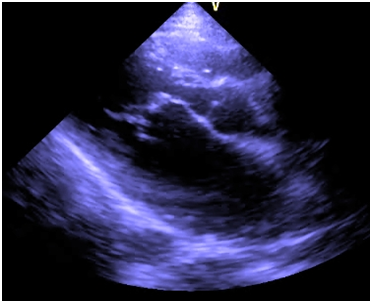

Investigations revealed hemoglobin value of 9g/dL, WBC count 4,000/cumm and platelet count was normal. Liver function test and renal function tests were normal. ECG showed the left ventricular hypertrophy. On chest X-ray there was a normal cardiac silhoutte and a normal lung parenchyma. Transthoracic echocardiography showed parachute-like mitral valve with a severe mitral stenosis (mitral valve size: 0.6 cm2, pressure gradient (Pg: 20 mmHg) causing obstruction to flow Figure 1. Aortic valve was bicuspid with a mild to moderate aortic stenosis (Pg: 40 mm Hg) Figure 2. Severe post-ductal coarctation of aorta with a diastolic tailing was seen on suprasternal view Figure 3. There was a Tiny mid muscular ventricular septal defect with left to right shunt. Small size patent ductus arteriosus with bidirectional shunt mainly left to right was present. Severe tricuspid regurgitation secondary to severe pulmonary hypertension (Right Ventricular systolic pressure = 84mmHg). Pulmonary artery was grossly dilated. There was mild left ventricular hypertrophy with a normal global systolic function and a normal ejection fraction. CT angiography revealed post ductal coarctation of aorta with patent ductus arteriosus with enlarged pulmonary trunk.